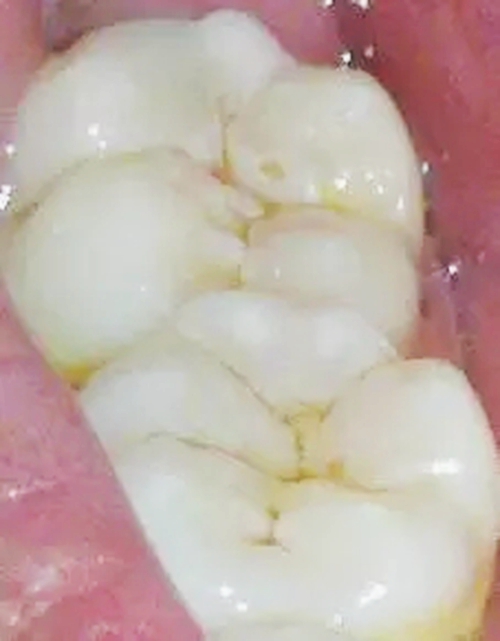

2,中齲

2.webp.jpg

齲壞已達牙本質淺層,臨床檢查有明顯齲洞,可有探痛,對外界刺激(如冷、熱、甜、酸和食物嵌入等)可出現(xiàn)疼痛反應,當刺激源去除后疼痛立即消失,無自發(fā)性痛。